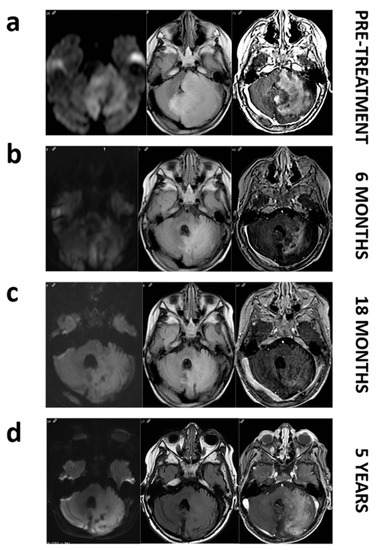

To assess the clinical relevance in the detection of BRAF V600E mutation, we present a case report of the 2-year-old patient LI.31. This patient was diagnosed with unresectable cerebellar ganglioglioma in 2012 and progression of his disease was objectified despite treatment with chemotherapy and radiotherapy. Two years later, MRI images showed a large cerebellar hemisphere and brainstem tumor crossing midline with high signal intensity on the T2-weighted scan. Substantial mass effect was noted, with obliteration of fourth ventricle. The analysis of the solid biopsy revealed BRAF V600E mutation by conventional PCR. Thereby, patient started treatment with 2 mg/kg of dabrafenib twice daily. Follow-up imaging within 6 months showed a reduction in mass effect and tumor volume with a notable decrease in tumor enhancement on contrast-enhanced MRI images, consistent with a partial response based on RANO criteria. Nowadays, patient upholds five years of stable disease with maintenance therapy (Figure 1). As shown in Table 3, when liquid biopsies of this patient were analysed, only the serum sample demonstrated concordance with the results obtained in the previous solid biopsy, positive for BRAF V600E mutation, whereas plasma analysis revealed a WT mutational status.

Figure 1. MRI images of patient LI.31 before and during dabrafenib treatment. Pretreatment images (a). Axial FLAIR image shows a large mass affecting left cerebellar hemisphere and pons with a marked mass effect on fourth ventricle. Axial diffusion (DWI) image reveals restricted diffusion within the mass. Axial T1 postcontrast image depicts intense enhancement. Follow up at 6, and 18 months (b,c). Axial FLAIR, DWI and post-contrast demonstrate a decrease in the mass extension and in the mass effect with a progressively enhanced shrinkage. Follow-up at 5 years (d). We do not notice a regrowth on axial FLAIR and even if enhancement reappears, restricted diffusion remains absent.